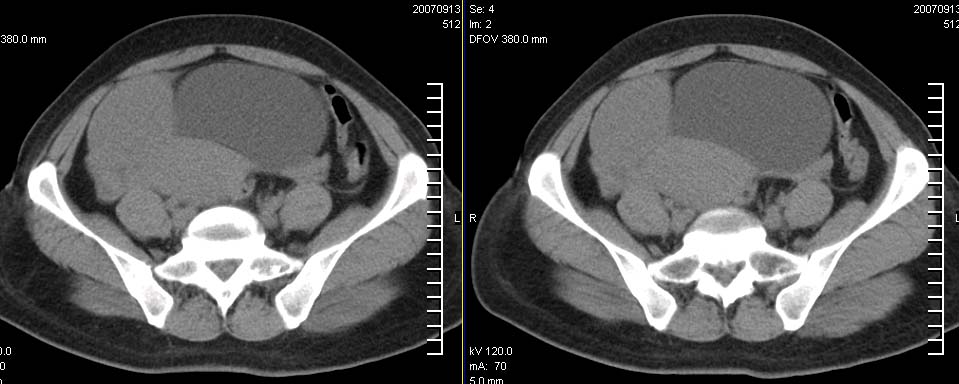

标题: CT9722:卵巢巨大占位,约10*18*21CM大小 [打印本页]

标题: CT9722:卵巢巨大占位,约10*18*21CM大小

卵巢巨大占位,约10*18*21cm大小

为什么就说它来源于卵巢呢?肠系膜同样可以啊?

右侧卵巢的巨大占位,病灶大部分呈实性,以恶性可能大。

考虑右侧附件来源肿瘤--囊腺瘤可能性大,子宫增大,建议增强扫描.

右侧附件区巨大囊性肿块,边缘光滑,密度较高,左侧缘由多个低密度区,首先考虑囊腺瘤可能。